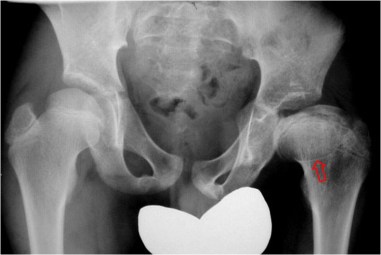

SIGNOS DEL PSOAS-ILIACO, GLÚTEO MEDIANO Y OBTURADOR INTERNO

Presentamos estos tres signos por tener el mismo significado.

Son signos radiológicos de derrame articular en la cadera, visibles en la proyección anteroposterior. Consisten en el abultamiento de las densidades de estos músculos (el psoas-ilíaco es medial a la cabeza y cuello femorales, el glúteo mediano es lateral al cuello y el obturador interno es superomedial al acetábulo) con el consiguiente desplazamiento de los planos grasos adyacentes. Son signos inespecíficos y pueden verse en sinovitis transitoria, artritis séptica y otras causas de derrame articular.

En estas imágenes ampliadas se explican los detalles de los tres signos. La flecha verde marca el desplazamiento lateral del plano graso de separación de la cápsula articular y el glúteo mediano. La flecha naranja señala el mismo plano no desplazado, en el lado no patológico. La flecha amarilla marca el desplazamiento del plano de separación del músculo psoas-ilíaco mientras que la flecha azul señala el mismo plano no desplazado en el lado normal. Finalmente, la línea roja indica la situación del plano graso de separación de la cápsula articular y el músculo obturador interno.

No debe confundirse el Signo del psoas-iliaco con el Signo del psoas, que consiste en el borramiento del margen del músculo visible en algunas apendicitis (excepcionalmente) y otras patologías. El borramiento también puede verse por cuestiones técnicas de la radiografía, solapamiento de material fecal, etc, por lo que resulta muy inespecífico.